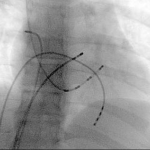

However, I also have personal experience of >1000 electrophysiology and catheter ablation procedures. I am also an expert device implanter, again with >1000 pacemaker, defibrillator and biventricular (resynchronisation, CRT) device implants.